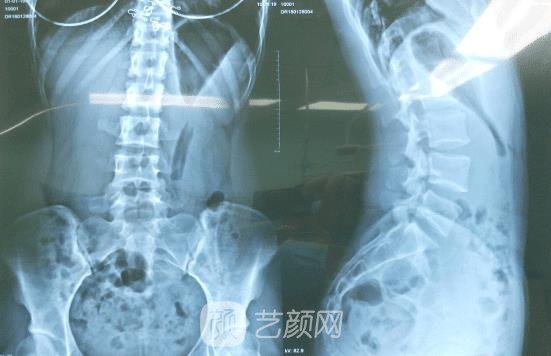

在面诊的时候,医生看了一下我的腿部情况之后,还拍了个片子,帮我详细的设置了一下矫正的方案,之后医生告诉我,等完成矫正之后,腿型看起来就会比较美观了,我心里特别的开心。